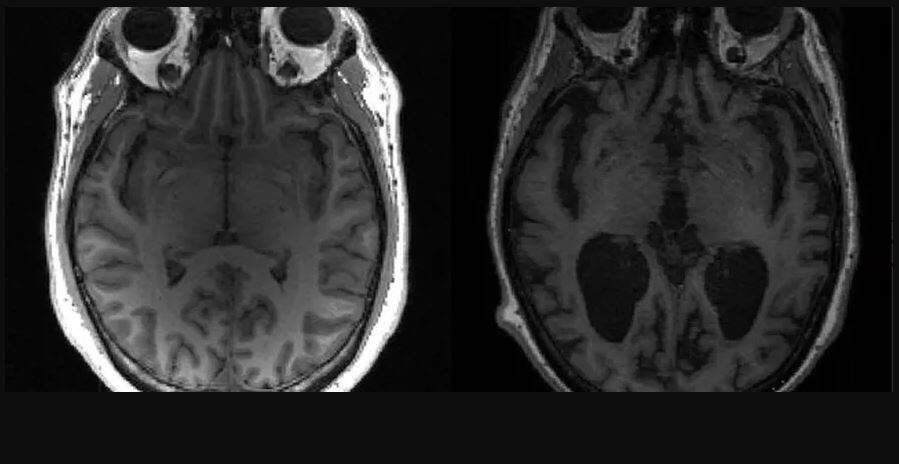

Imagem mostra cérebro saudável à esquerda e cérebro com Alzheimer à direita. (Foto: Reprodução)